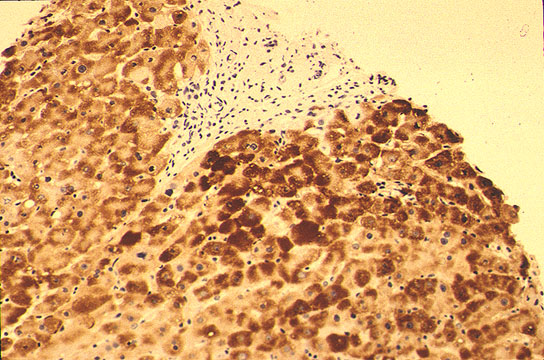

Surface antigen in hepatocyte

Fig 95 - Surface antigen in hepatocyte: It is present as brown granules only in the cytoplasm of hepatocyte. The nuclei are stained blue with hematoxylin counterstain.(Immunoperoxidase technique).

Core antigen in hepatocyte

Fig 96 - Core antigen in hepatocyte: At difference with surface antigen It is present in the nuclei of hepatocyte. Here the virus replicates and acquires the envelop of surface antigen in the cytoplasm.